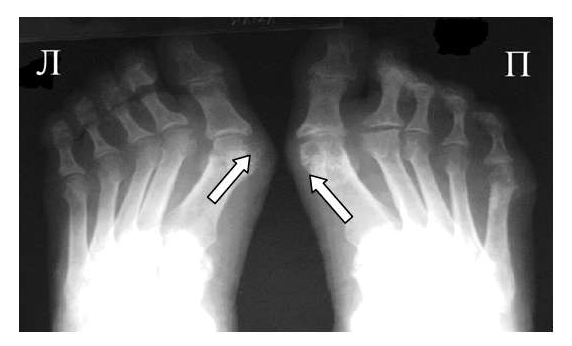

Рентгенография - в начальной стадии при подагре почти не дает информации; при длительном течении, когда кристаллы накапливаются внутри кости, их видно как четкие округлые образования - “пробойник ”.

При пирофосфатной артропатии иногда можно увидеть кальцификацию суставного хряща.